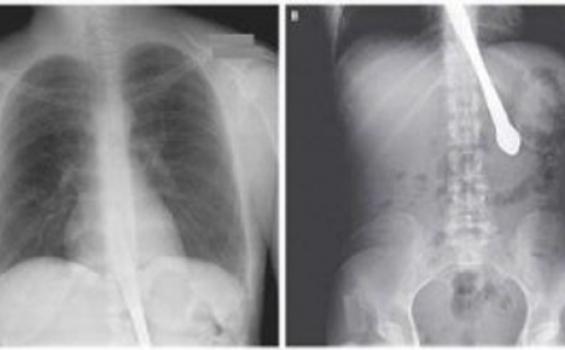

TRIBUNNEWS.COM - Seorang wanita berusia 30 tahun tak sengaja menelan pisau saat ia sedang tertawa. Kejadian itu bermula saat wanita yang punya riwayat bulimia itu sedang menunjukkan pada temannya bahwa ia tak lagi punya refleks memuntahkan.

Kemudian ia memasukkan pisau ke mulutnya dan tertawa, pada saat itulah pisaunya terlepas dan ia menelannya. Beruntung dokter berhasil mengambil pisau tersebut dan tak ada kerusakan fisik yang dialaminya. Sebelumnya ia juga pernah menelan pisau. Ia kemudian dirujuk untuk berkonsultasi ke psikiater.